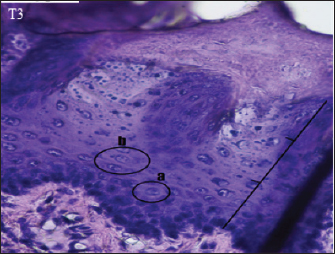

The histopathological appearance of the rat tongue epithelium in the T3 group was close to that of normal epithelium. It is characterized by regular stratification cells. Variations in the shape and size of the nucleus are slight. Hyperchromatic nuclei are found in the basal and parabasal layers. Irregular polygonal cell shapes in the spinosum layer and oval cell shapes in the granulosum layer were also seen in this group (Fig. 5).

Fig. 5. Histopathological appearance of the rat tongue epithelium in group T3, microscope at ×400. (a) irregular polygonal cell shape in the spinosum layer; (b) oval cell shape in the granulosum layer.